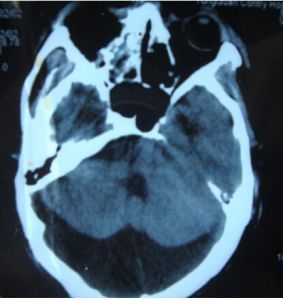

發病部位

枕大池(又稱小腦延髓池),位於顱後窩的後下部,小腦下面、延髓背側面與枕鱗下部三者之間。 向前經小腦溪通第四腦室;向前外經延髓側面通延髓池。三維斷面均可顯示。

枕大池囊腫